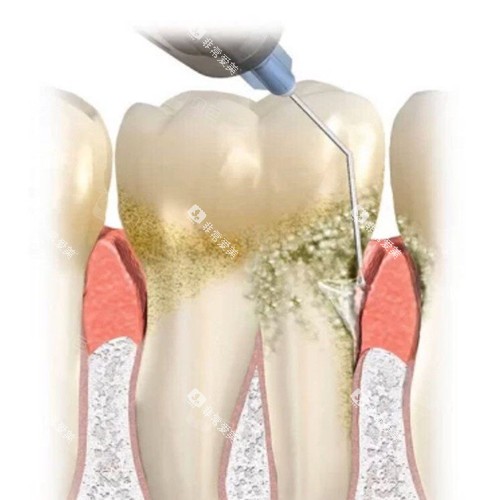

牙周科的医师们在牙周疾病的诊断和治疗方面有着丰富的经验。

他们不仅能够熟练进行牙周基础治疗,如洗牙、刮治等,还擅长治疗一些重的的牙周炎病例。

通过个性化的治疗方案和系统的牙周维护,帮助患者修复口腔健康,预防牙齿松动和脱落。

例如,可靠的根管治疗设备可以提高根管治疗的精度和效率,减少患者的就诊次数;超声洁牙机可以更有效地清除牙齿表面的牙结石和菌斑,保护患者的口腔健康。